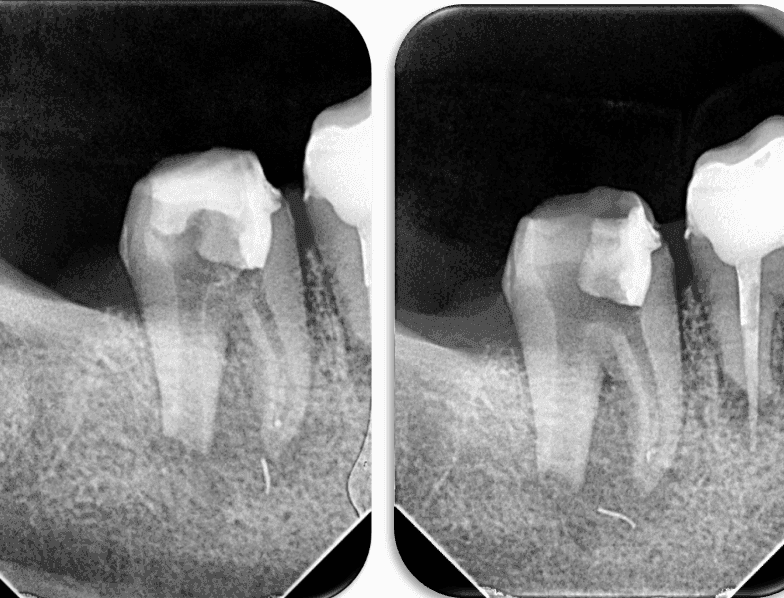

Daha sonra kontrol röntgeni alındı ve eğenin konumu tespit edildi (RESİM 4).

RESİM 4: Kırık eğenin ve taşkın gutanın kök ucundan apikale ilerlediği tespit edildi